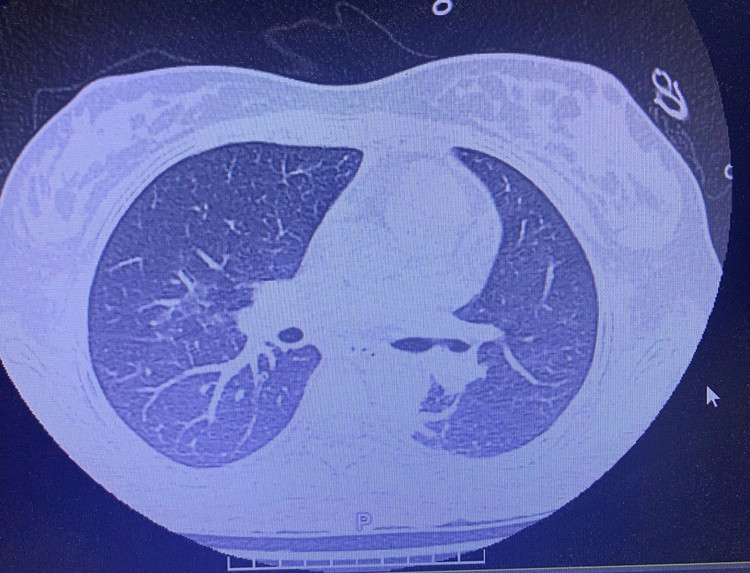

Bệnh nhân nữ, 19 tuổi, nhập viện trong tình trạng khó thở, sốt cao, ho đờm. Chẩn đoán ban đầu là viêm phổi nặng. Chỉ trong vòng 3 ngày, tình trạng hô hấp suy sụp nhanh chóng, hình ảnh X-quang và CT phổi cho thấy phổi trắng xóa hai bên – dấu hiệu điển hình của Hội chứng suy hô hấp cấp tiến triển (ARDS), một biến chứng nguy kịch thường gặp ở những ca viêm phổi nặng.

Hình ảnh tổn thương phổi trên phim chụp - Ảnh BVCC